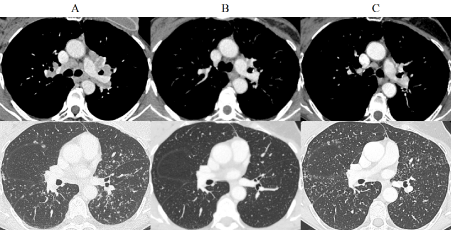

A CT-scan performed in September 2018 showed, in comparison to the one performed in 2017 (Figure 1), a slight increase in the size of a right hilar lymph node, subpleural micronodules in the posterior segment of the right upper lobe and in the anterior segment of left upper lobe. There was also a miliary pattern in the inferior part of both upper lobes with subpleural locations adjacent to the fissures. A bronchofibroscopy was performed with several biopsies of the bronchial spurs which confirmed a granuomatous giganto-cellular inflammation in favor of a sarcoidosis (or sarcoid-like) relapse. The bronchiolar-alveolar lavage cellular analysis showed 37% of lymphocytes, mostly TCD4+ with a ratio TCD4+/TCD8+ of 3.

Figure 1. Injected thoracic CT-scan axial with mediastinal and parenchymal windows. (A) 2015 Mediastinal and hilar enlarged lymph nodes, subpleural and parenchymal micronodules (B) 2017 Régression of lymphadenopathies and of the micronodules (C) 2018 Reactivation of the subpleural and parenchymal micronodules (but not of lymph nodes)